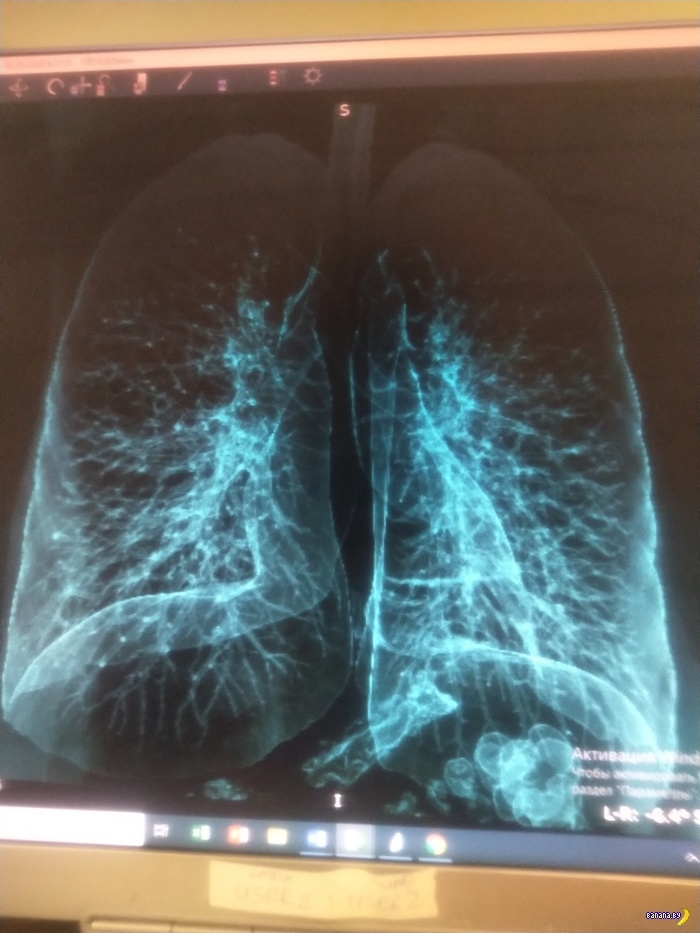

Нет симптомов COVID-19, но лёгкие уже поражены

Пульмонолог объяснил ужасающий "эффект матового стекла"

Японские учёные, исследовавшие результаты, полученные при проведении компьютерной томографии людям, переболевшим COVID-19 без явных симптомов, выявили поражение лёгких, которое называется "эффектом матового стекла". Причину этого явления объяснил пульмонолог Александр Пальман, доцент кафедры госпитальной терапии Первого МГМУ им. Сеченова.

Как известно, на "карантинном" лайнере Diamond Princess диагноз COVID-19 был поставлен 104 пассажирам. При этом у 76 из них симптомы отмечены не были. Тем не менее у 41 "бессимптомного" больного при КТ обнаружили изменения, которые специалисты называют "эффектом матового стекла".

Это утвердило учёных в мысли, что бессимптомное течение COVID-19 для носителей вируса не проходит бесследно.

Комментируя результаты исследования в беседе с газетой "Взгляд", Александр Пальман отметил, что причиной этого эффекта может стать любая вирусная инфекция или аллергия. Само по себе это явление временное, с выздоровлением оно обычно проходит и не указывает на какое-либо поражение лёгких, уверен пульмонолог.

"Матовое стекло" - это чисто рентгенологический термин, и, как всякое инструментальное обследование, это не диагноз, а, условно говоря, картинка. На снимке отдалённо это напоминает лёгкие в тумане. Затуманенный участок лёгких - неспецифический воспалительный признак, который соизмеряется с соответствующей клинической картиной. Это может быть и при вирусной ситуации, и при бактериальной, и при аутоиммунной агрессии, и при аллергической реакции", - говорит Пальман.

По его словам, "эффект матового стекла" невозможно рассмотреть на обычном рентгеновском снимке. Зато при помощи компьютерной томографии можно увидеть самые мелкие структуры лёгких. При этом у снимков КТ есть ещё одно свойство - они чрезвычайно чёткие. Из-за этого врачи могут увидеть нечто такое, чему не могут дать точного объяснения.

Пальман отметил, что если КТ делать при любых вирусных инфекциях, то у большинства пациентов можно будет обнаружить "страшные" изменения в лёгких. Особенно заметно это будет, если человек болен гриппом. Но такие изменения можно отметить даже у совершенно здоровых людей.

"Я не уверен, что изменения у этих пациентов с коронавирусом, которые были на круизном лайнере, на 100% связаны именно с этой инфекцией. В данном случае просто можно говорить о вероятности", - считает Пальман.

Если в заключении после КТ будет написана фраза "отмечаются участки по типу матового стекла", это ещё не повод для серьёзного беспокойства или паники. Просто снимок говорит о том, что пациенту стоит посетить пульмонолога, который и объяснит, что же такое происходит с лёгкими."